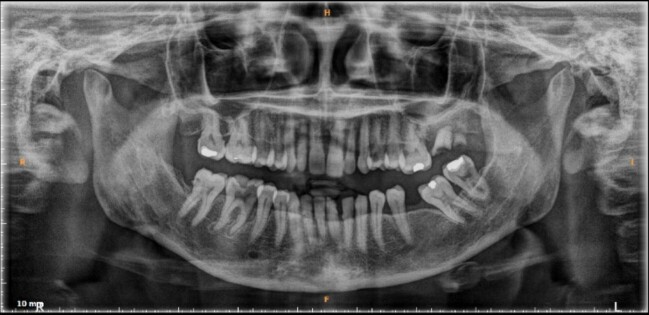

Lemierre's syndrome is marked by presence of septic thrombophlebitis in the internal jugular vein. This case report describes a 57-year-old woman who presented with a progressively swelling neck with onset 1 day prior to admission. She had a history of untreated dental infection. Physical examination revealed slightly increased blood pressure, at 140/80 mmHg, and a painful, erythematous, warm swelling in the mid area of the neck. Ultrasound of the neck revealed occlusive intraluminal thrombus in the right internal jugular vein, a computed tomography (CT) scan with contrast showed that there was a blockage in the right jugular vein. The mainstay treatment for Lemierre's syndrome is antibiotics, while administration of anticoagulants remains controversial. The patient was treated conservatively, with administration of antibiotics and anticoagulant. Several days later the patient's condition had improved significantly, with less pain and reduced swelling.

Abstract Image